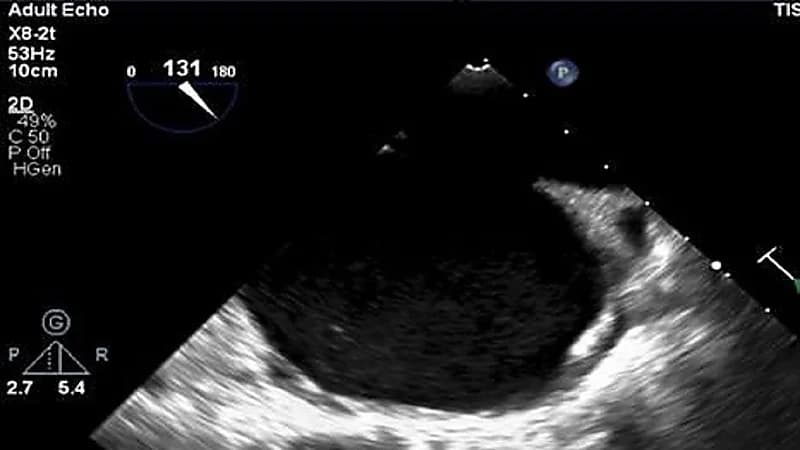

تمكن فريق جراحي في مدينة الملك فهد الطبية من إنقاذ حياة إمرأة حامل مصابة بأمراض القلب تزامنت مع ولادتها في العقد الثالث من عمرها.

وأوضح الفريق الطبي أن المريضة تعاني من ارتفاع شديد في ضغط الشريان الرئوي وعيب خلقي في القلب إضافة إلى ضعف شديد بعضلة البطين القلبي الأيمن.

وخضعت لعملية قيصرية وربط لأنابيب فالوب ذات خطورة عالية حيث وصفها الأطباء بالعملية المعقدة إلا أنها تكللت بالنجاح